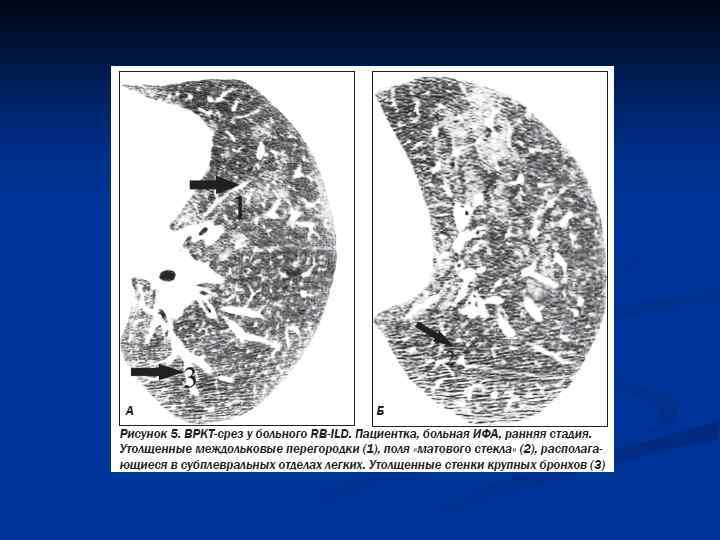

КТВР Ретикулярные изменения, обычно двухсторонние, отчасти связаны с тракционными бронхоэктазами; часто наблюдаются признаки формирования сотового легкого; участки «матового стекла» распространены в меньшей степени, чем ретикулярные изменения; характерны нарушения архитектоники, отражающие легочный фиброз; патологические изменения характеризуются неоднородностью и локализованы преимущественно в периферических и базальных отделах; зоны «матового стекла» могут уменьшаться в процессе лечения больных, однако наиболее характерно прогрессирование фиброза с формированием сотового легкого; точность диагностики ИФА по данным КТВР достигает 90 %